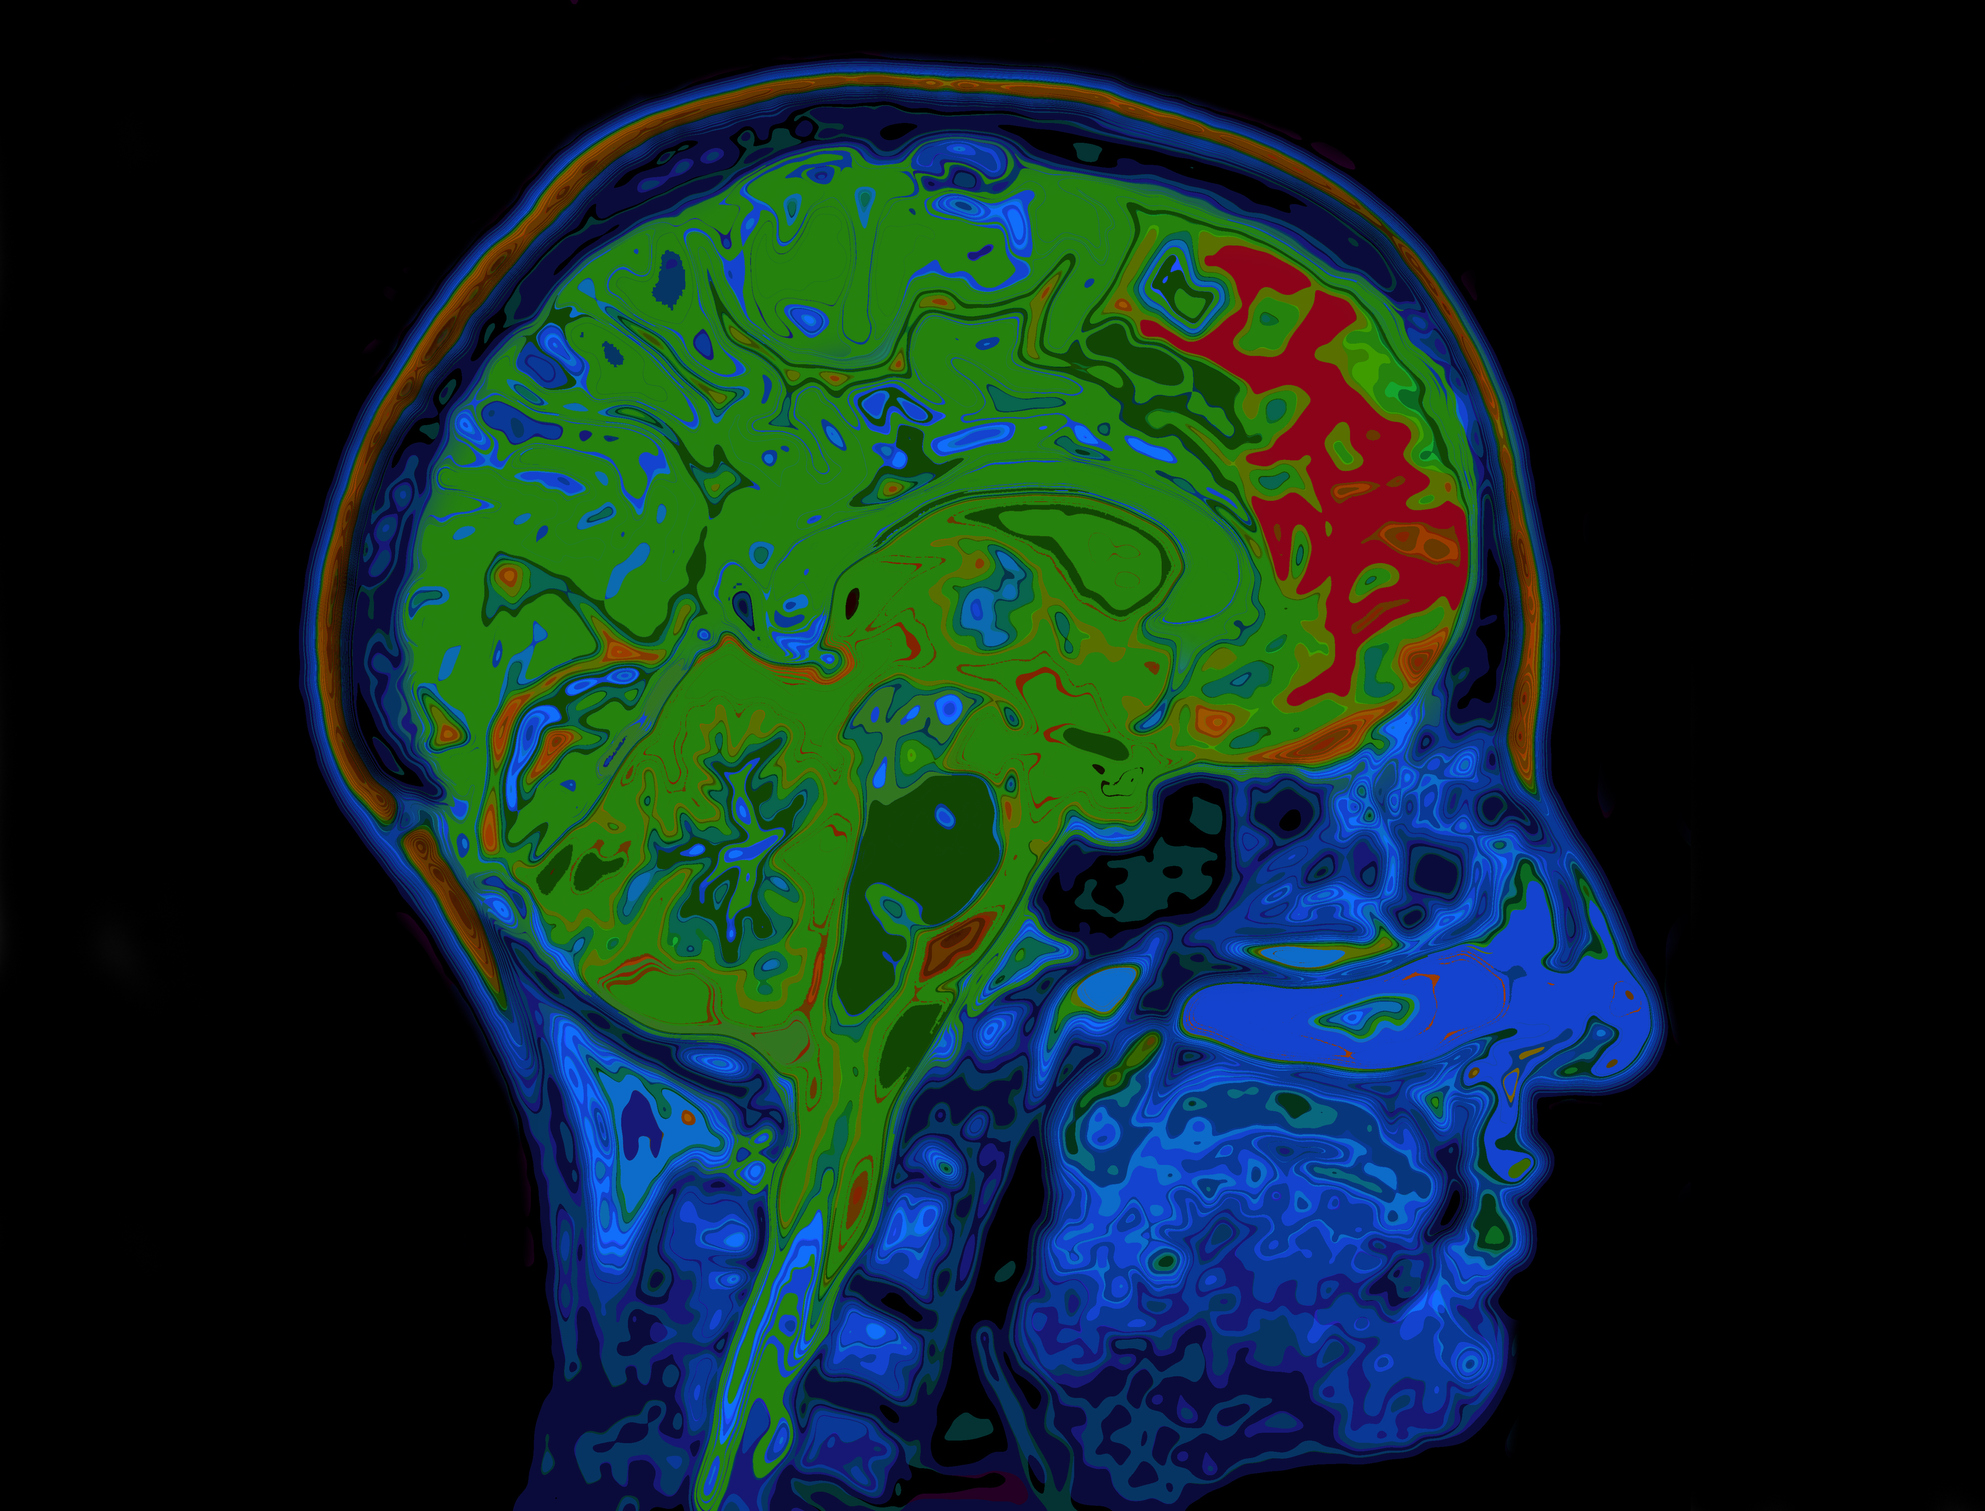

The Latest Treatments for brain tumours

BRAIN CANCER and BRAIN TUMOURS- Latest Treatments; PART 1